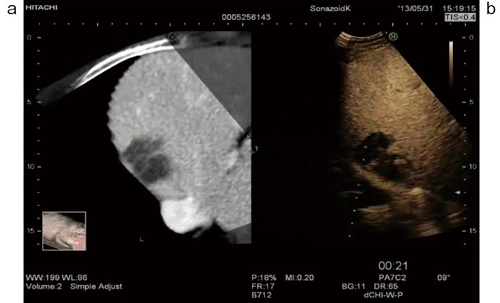

RVSのシンプル・アジャスト機能

a:CT画像 b:CEUS画像

双方のメルクマールとなるポイントにアジャスト点(+マーク)を設定し,

位置合わせを行う。